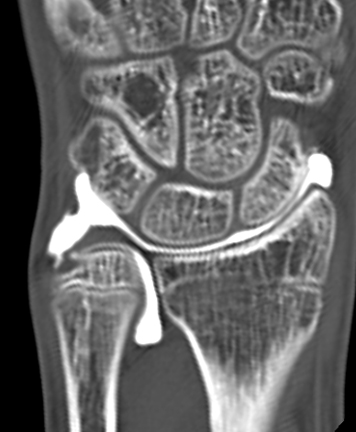

単純X線の他、MRI、手関節造影/CTを行います。単純X線では、TFCC自体は映りません。しかし、骨形態の評価、とくに突き上げ症候群の評価に有用であり、必須の検査の1つです。MRIではTFCCの損傷の有無を評価します。また、ECU腱鞘炎などその他の障害/疾患の有無を確認します。しかしながら、MRIではTFCCの詳細な評価が難しい場合があり、手関節造影/CTが必要となることがあります。手関節造影/CTでは、造影剤を橈骨手根関節内および遠位橈尺関節内に注入しTFCCの円盤部や末梢部、表層部、および小窩(Fovea)部などでの断裂形態を確認します。その他、手根骨間靱帯損傷や手関節尺側部の骨形態について評価します。

【手関節造影】

【手関節造影後CT】